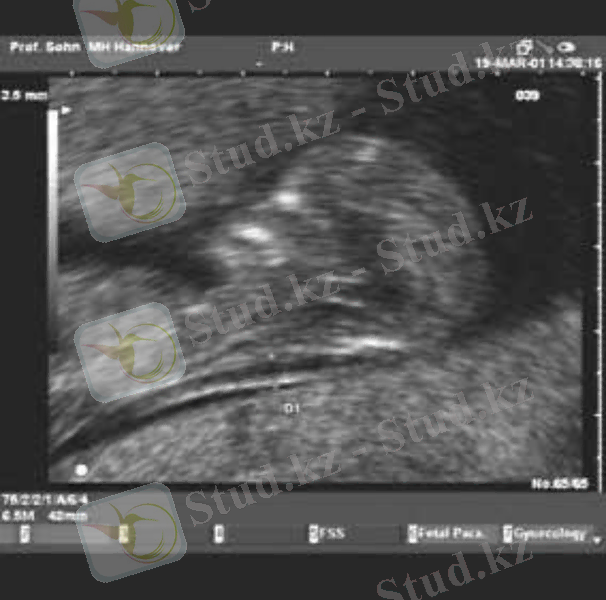

Хорион және плацентобиопсия аз мөлшерде хорион бүрін не плацента үзіндісін алу үшін жүргізіледі.

Бұл УДЗ бақылау арқылы трасабдоминальды және трасцервикальды жолмен жүргізіледі.

Асқыну қаупі - 2 %